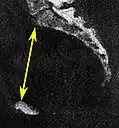

| Pelvic outlet | Sagittal pelvic outlet diameter |

Same, but may require minor side-to-side scrolling to visualize both end points. | The closest bony points of the sacrococcygeal joint and the pubic bone next to the symphysis. This is also called the obstetric anteroposterior diameter of the pelvic outlet, to distinguish from the anatomic one which includes the coccyx.[7] However, the coccyx is normally pushed away during childbirth by laxity in the sacrococcygeal joint.[8] | 9.5 to 11.5 cm.[6] |